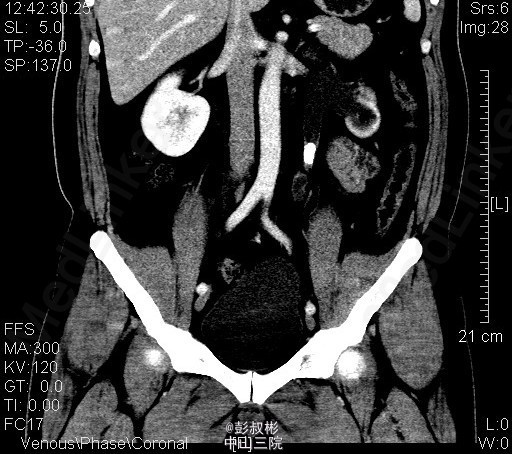

1、体检发现左输尿管结石2月 2、患者2月前体检发现左输尿管结石,无腰痛,无其他部位反射痛,无发热,无恶心,当时未给予治疗。今为求进一步治疗来我科住院,起病以来患者一般情况尚可,体重无下降。

3、查体:双肾区无红肿、隆起,左肾区叩击痛(-),右肾区叩击痛(-),左侧肋脊点、肋腰点压痛(-),右侧肋脊点、肋腰点压痛(-)。腹平软,左侧输尿管走行区压痛(-),右侧输尿管走行区压痛(-),膀胱区无膨隆,压痛阴性 4、辅助检查: 我院 腹部平片 左输尿管上段结石 ;泌尿系b超 前列腺增大;右肾多发结石;左肾形态失常;左输尿管上段结石并左肾积液。CT示左输尿管上段结石、左肾小结石

5、诊断:左输尿管上段结石并左肾积液 6、入院后予以完善术前检查,未见明显手术禁忌,在全麻下行“单孔腹腔镜下左输尿管切开取石术”,术后予以一级护理,心电监护,低流量吸氧,营养支持,抗炎对症治疗。术后注意观察事项:保持引流管及尿管通畅,留意尿量及引流量